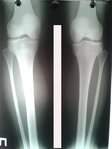

Дата операции 06.05.2016г.

Исходник - 27 лет.

У пациентки двусторонняя ротация